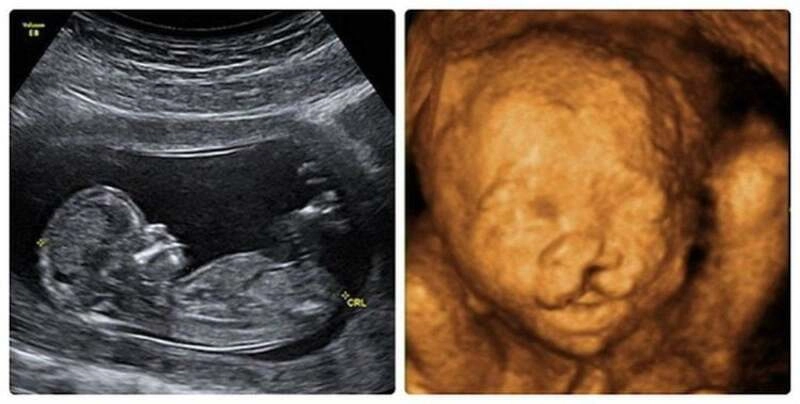

Với sự phát triển của công nghệ siêu âm hiện nay, việc tầm soát dị tật vùng hàm mặt đã trở nên chính xác hơn rất nhiều. Cha mẹ có thể biết được tình trạng của con qua các mốc thời gian sau:

Trong thai kỳ: Bác sĩ có thể quan sát thấy hình ảnh hở hàm ếch qua siêu âm 3D/4D từ tuần thứ 13 của thai kỳ. Tuy nhiên, thời điểm “vàng” để quan sát rõ nhất các chi tiết ở môi và mũi là từ tuần thứ 18 đến 22. Việc phát hiện sớm giúp gia đình có sự chuẩn bị tâm lý và tìm hiểu trước về lộ trình điều trị ngay khi bé chào đời.